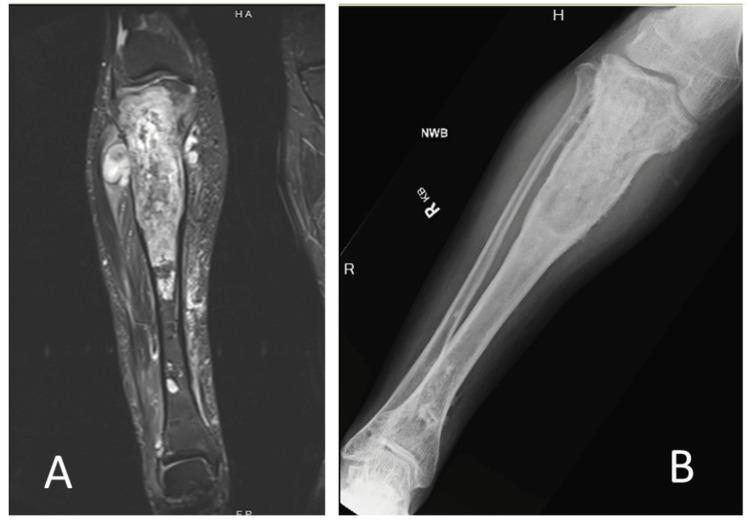

Ollier's disease is a rare syndrome characterized by multiple enchondromas with the potential for malignant transformation. The treatment for secondary chondrosarcoma is surgical resection, which can be a morbid procedure depending on the location and size of the tumor. We present a successful limb salvage in which the majority of the tibia was removed and replaced with a megaprosthesis. The complex reconstruction in this case required the use of a novel uncemented stem.

骨软骨瘤病是一种罕见的综合征,其特征为多发性内生软骨瘤并有恶变的可能。继发性软骨肉瘤的治疗方法是手术切除,根据肿瘤的位置和大小,这可能是一个创伤性较大的手术。我们展示了一例成功的保肢手术,其中大部分胫骨被切除并用一个大型假体进行了置换。该病例中的复杂重建需要使用一种新型的非骨水泥型柄。